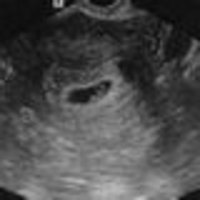

К концу 3-ей недели (на 6-8 день после оплодотворения) плодное яйцо внедряется в стенку матки.

На сроке 4-5 недель длина тела эмбриона составляет всего 2-

До 8-й недели можно сделать необязательное первое УЗИ при беременности для подтверждения беременности и определения в каком месте закрепилось плодное яйцо. Но можно и обойтись без нее, опытный гинеколог путем обычного осмотра может определить беременность.